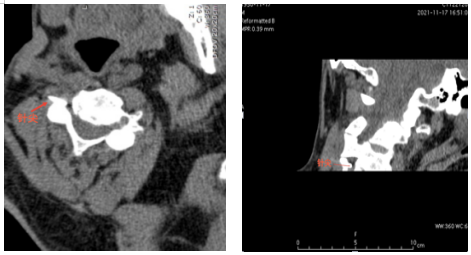

经人介绍,李爹爹来到了湖北省第三人民医院疼痛科二病区就诊,杨庆红主任经过查体后诊断其为带状疱疹性神经痛,疼痛范围为颈丛神经分布区域。李爹爹住院后,医生予以口服普瑞巴林胶囊及泰勒宁止痛,但效果不佳,后进行了超声引导下颈丛神经阻滞,但效果维持时间不长,最终杨庆红主任决定为患者施行CT引导下颈丛神经脉冲射频微创手术。但李爹爹本身是一位肝硬化患者,胸壁静脉及颈部静脉怒张,再加上颈部本身结构复杂,存在多根大血管,容易引起出血。

为了确保手术安全顺利进行,术前杨庆红主任组织科室充分讨论病例,制定了详细的手术方案。11月21日,在放射科主管技师胡卫的协助下,杨庆红主任带领疼痛科医生李圣洪在CT引导下找准穿刺路径、角度及深度,为李爹爹实施了颈丛神经脉冲射频微创手术,术后当晚,李爹爹就感觉疼痛明显缓解,人也轻松了一大截。目前患者疼痛控制良好,几乎没有疼痛。